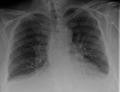

Chest X-ray

Chest radiograph of a lung with distinct Kerley B lines, as well as an enlarged heart (as shown by an increased cardiothoracic ratio, cephalization of pulmonary veins, and minor pleural effusion as seen for example in the right horizontal fissure. Yet, no obvious lung edema is seen. Overall, this indicates intermediate severity (stage II) heart failure.

Chest X-rays are frequently used to aid in the diagnosis of CHF. In a person who is compensated, this may show cardiomegaly (visible enlargement of the heart), quantified as the cardiothoracic ratio (proportion of the heart size to the chest). In left ventricular failure, evidence may exist of vascular redistribution (upper lobe blood diversion or cephalization), Kerley lines, cuffing of the areas around the bronchi, and interstitial edema. Ultrasound of the lung may also be able to detect Kerley lines.[43]